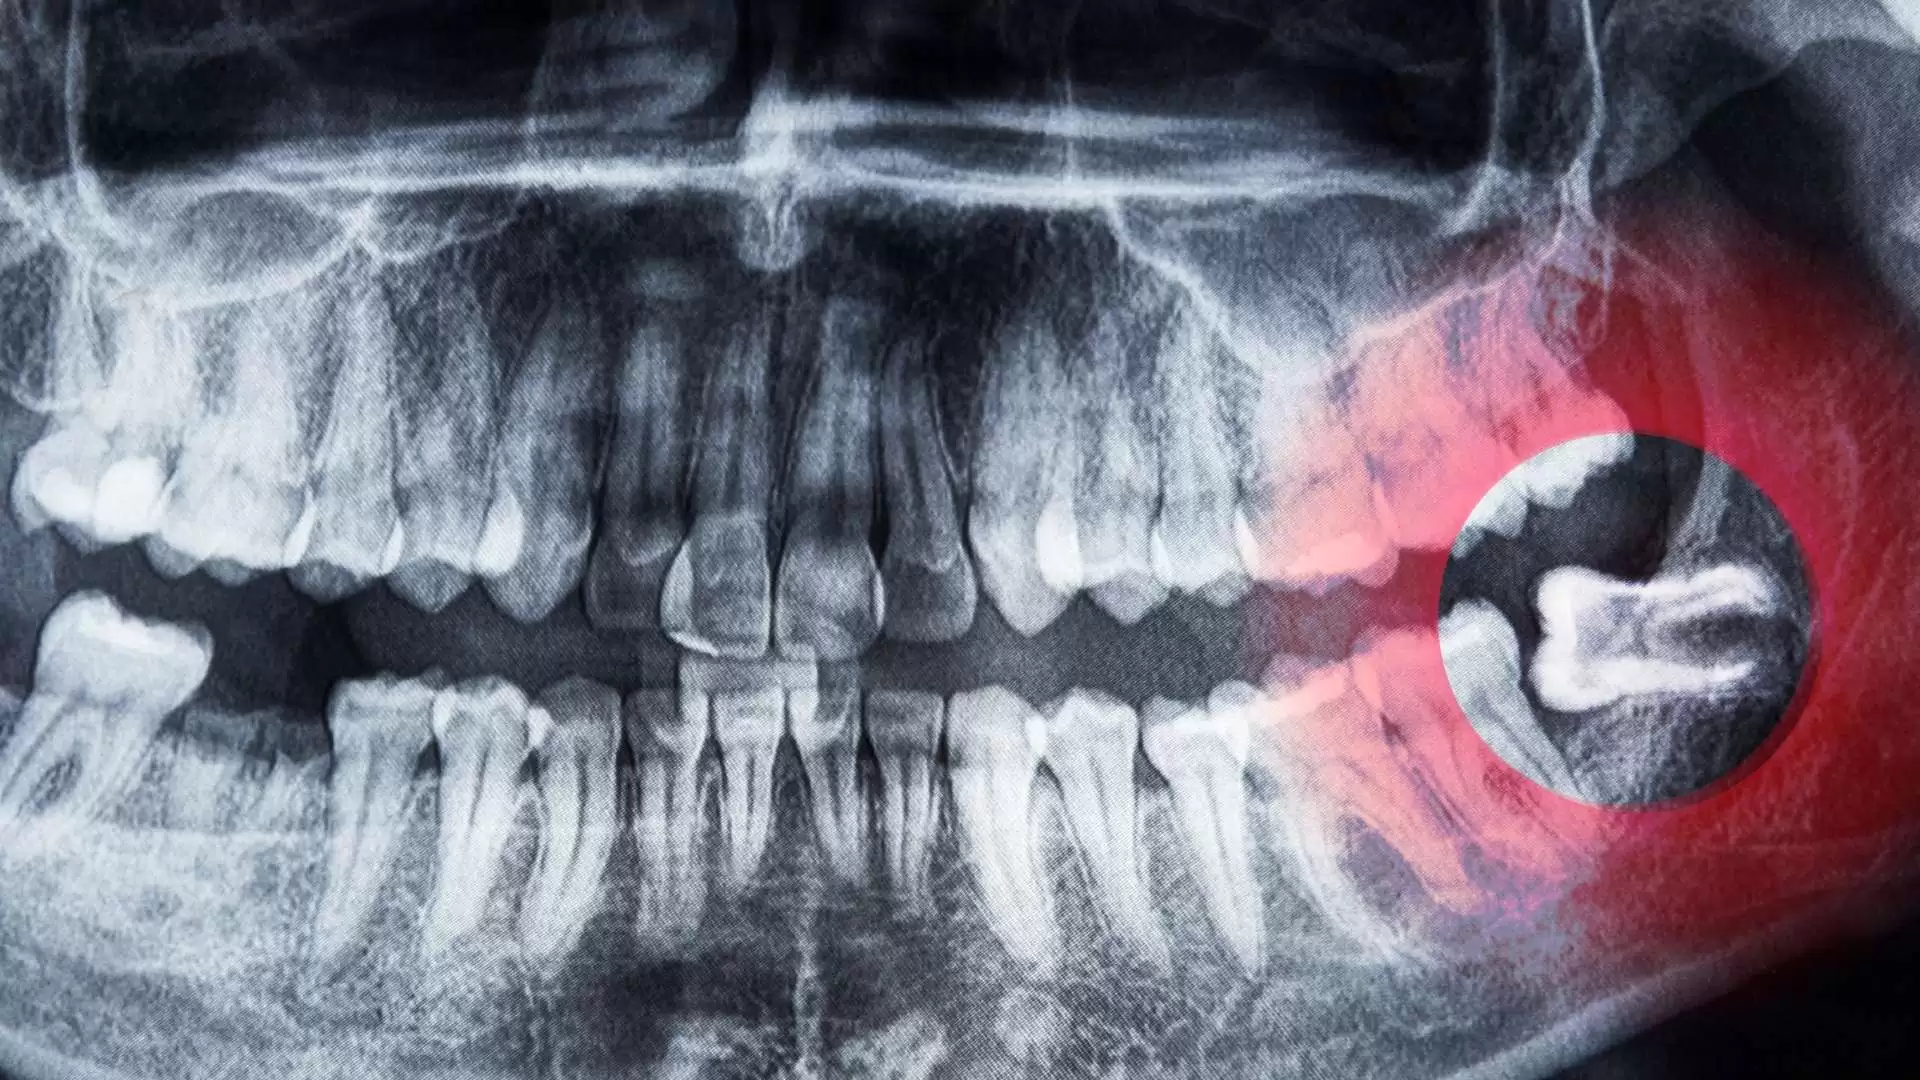

Wisdom teeth, or third molars, don’t always require removal. Some people have enough space for them to erupt fully without causing problems, while others may experience pain or complications that mean extraction is the best choice.

Regular dental exams and X-rays allow your dentist to track how your wisdom teeth develop and recommend the safest, most effective plan. Early monitoring can prevent emergencies and discomfort.